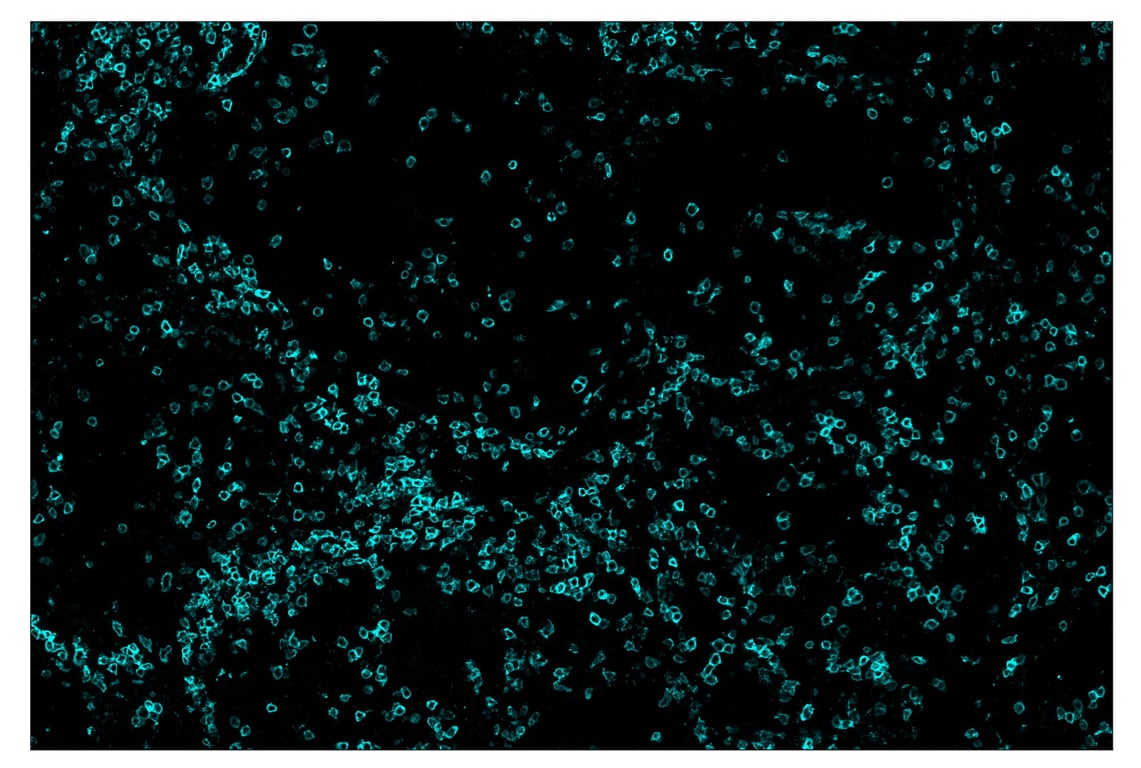

SignalStar™ immunohistochemical analysis of paraffin-embedded human non-small cell lung carcinoma using CD3ε (D7A6E™) & CO-0001-750 SignalStar™ Oligo-Antibody Pair #51754 (cyan). All fluorophores have been assigned a pseudocolor, as indicated. Staining was performed on the Leica BOND Rx.

Immunohistochemistry Image 5: CD3 epsilon (D7A6E<sup>™</sup>) & CO-0001-750 SignalStar<sup>™</sup> Oligo-Antibody Pair